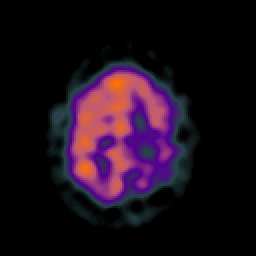

SPECT TC Study #5 -- Slice #42

[Home][Help][Clinical][Tour 1][Tour 2][Tour 3] Slice 42